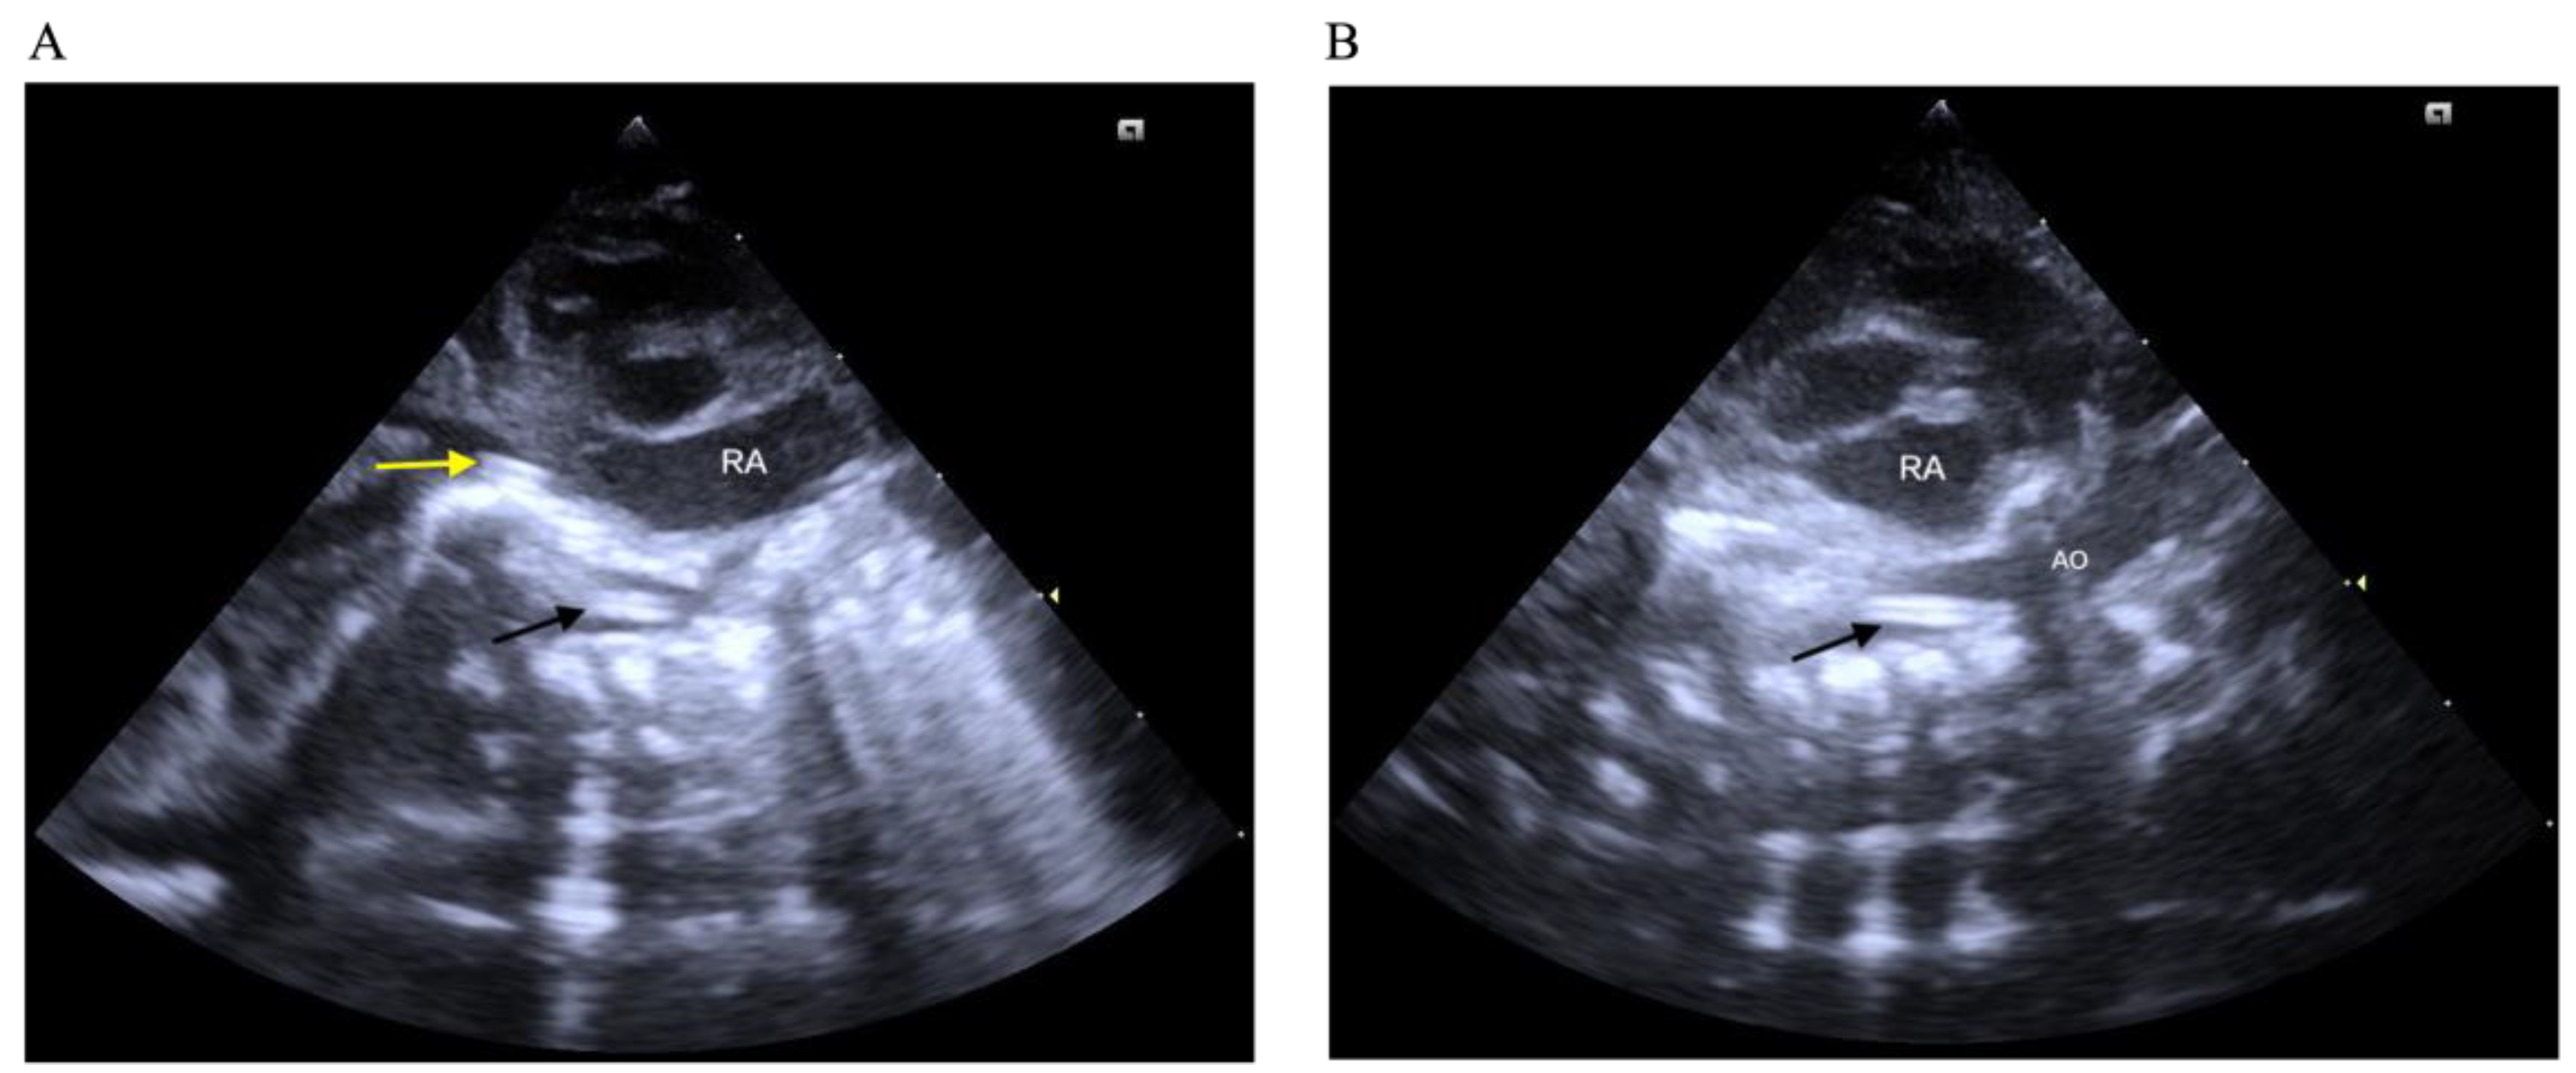

- PoCUS can identify the location of the umbilical catheter more accurately and imme-diately than traditional radiography.

- PoCUS should be considered as a standard tool for umbilical catheter placement.

- The use of PoCUS for catheter localization should be promoted in all NICUs.